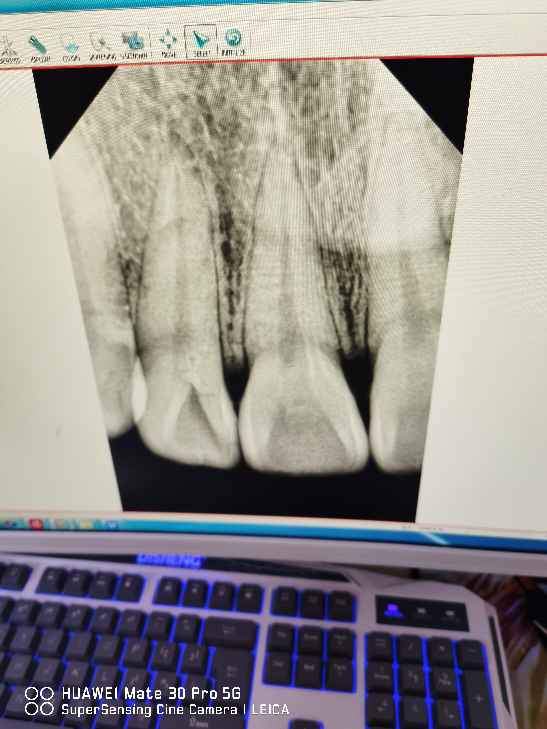

×î½üͻȻ·¢ÏÖÓÐÒ»¿ÅÑÀ³Ý±È½ÏºÚ£¬È¥Ò½ÔºÅÄÁËÆ¬×Ó£¬Ëµ¿ÉÄÜÊÇÑÀÖܲ¡£¬Òª²¹ÑÀÉõÖÁ¸ù¹ÜÖÎÁÆ£¬Âé·³Çë¸÷λ´óÀаïæ¿´Ò»Ï£¬Ð»Ð»¡£

´ÓÄú¿ÚÄÚÕÕÆ¬ÒÔ¼°¸ù¼âƬ¿´

1£©È£³Ý¿ÉÄÜÐԱȽϴó£¬ÑÀ³Ý³äÌîÖÎÁƾͿÉÒÔ£¨²¹ÑÀ£©£»

2£©Èç¹ûÈ£»µµ½ÑÀË裬ÔòÐèÒª¸ù¹ÜÖÎÁÆ£¬ £¨¿ÉÄÜÐÔÓУ©

3£©ÑÀÖܲ¡¿ÉÄÜÐÔ½ÏС